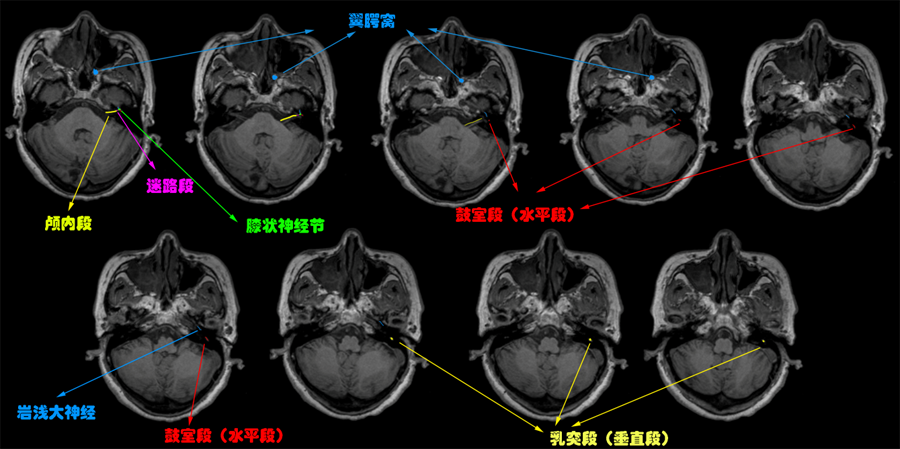

从上图可见,面神经出脑桥时,于脑桥小脑三角处与前庭蜗神经伴行,图中黄线即为面神经颅内段,为内听道段。后由内听道进入面神经管,续为迷路段(紫线)。迷路段为最狭窄的一段,但含有面神经所有四大纤维,“路窄车多”,非常容易因肿瘤、神经炎症等发生面神经压迫。迷路段的末端为膝状神经节(绿色)。膝状神经节后即分出岩浅大神经(蓝线)和面神经运动纤维。面神经运动纤维先后通过鼓室段(又称水平段,红线)和乳突

段(垂直段,黄色),其转弯处分出鼓索(感觉纤维)和镫骨肌神经。

面神经出茎突孔后会经过腮腺,最终分为五支,支配面部所有表情肌;岩浅大神经内含一般内脏感觉纤维,走行于翼腭管,至翼腭神经节(上后窦后上方,图2中蓝色标记),最终至泪腺、唾液腺,支配其分泌;关于翼腭神经节,在《三叉神经解剖——被四大核团掌控的一双胖子手》一文中提及,这个结构还是很重要的。图2用不同颜色标注了面神经的走行及分段。

再从图3巩固一下,图3黄线表示特殊内脏运动纤维(司头面部肌肉运动),紫线为一般内脏运动纤维(腺体分泌),蓝、绿线表示感觉纤维。